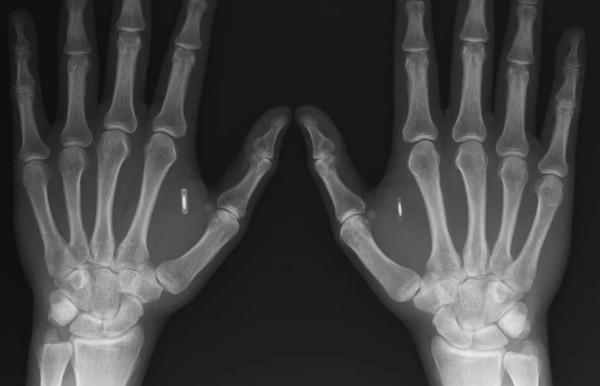

Con un escalpelo, Vladislav Zaitsev hace una incisión entre el dedo índice y el pulgar del paciente e introduce un pequeño cilindro de vidrio: un chip subcutáneo que le permitirá abrir la puerta de su oficina.

En 2015 captó la atención internacional al implantarse el chip de su tarjeta del metro de Moscú. Para conseguirlo diluyó la tarjeta en acetona para recuperar el chip, que cubrió con silicona, antes de introducirlo en el dorso de una mano. Filmó el procedimiento y lo divulgó en YouTube.

El disco, algo más pequeño que una moneda de cinco céntimos de euro, todavía se ve pero ha dejado de funcionar como tal: Zaitsev lo ha reprogramado con los datos de su tarjeta bancaria. Para divertirse con sus amigos, también se implantó imanes bajo la punta de los dedos.

Algunos chips han sido aprobados para un uso humano, pero los que utiliza Zaitsev están destinados a los veterinarios. Son fabricados en Taiwán y los compra por internet a un precio de 500 rublos (US$8).

En su pequeño apartamento, cobra 2.000 rublos (US$30) por el implante de un chip poco más grande que un grano de arroz. Afirma haber efectuado unas cincuenta operaciones.